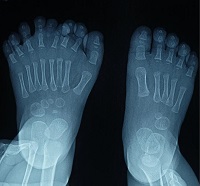

La polidactilia pediátrica es un trastorno congénito común de la mano y el pie que afecta el desarrollo y la psicología de los niños. Se clasifica en polidactilia postaxial, polidactilia preaxial y polidactilia central. De los tres tipos, la polidactilia central es la más rara, por lo que la literatura médica sobre su manejo es limitada. Ver más…